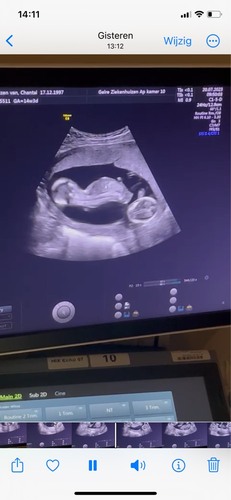

Momenteel 14 weken, ik krijg al sinds week 8 elke 2 weken echo's. Er is altijd wel verschil gezien tussen beide kindjes en vorige week was het niets om ons zorgen over te maken, 7 dagen later dus ineens wel. Het is dus zeker optijd ontdekt, ik hoop dat het inderdaad goed te behandelen is mocht dat nodig zijn...

Een wat late reactie. In vogelvlucht: Werd naar leiden doorgestuurd, toen geen TTS maar sFGR. Tot 27 weken onder controle in Leiden en met 28 weken opgenomen in het WKZ voor foetale controles 2x daags. Longrijping gehad en bijna dagelijks echo's omdat de kleine baby stagneerde in groei en de bloedvaten van de navelstreng niet optimaal meer werkte van de kleine baby.

Uiteindelijk op 17 november met 31+4 middels een spoed sectio wegens acute TTS bevallen van 2 prachtige dames Romy (1180 gram) en Esm茅e (1650) gram. Veel gebeurd, waaronder ook nog eens een RS virus met 2 weken beademing voor Esm茅e maar we zijn nu lekker 5 weken met zn allen thuis馃挄